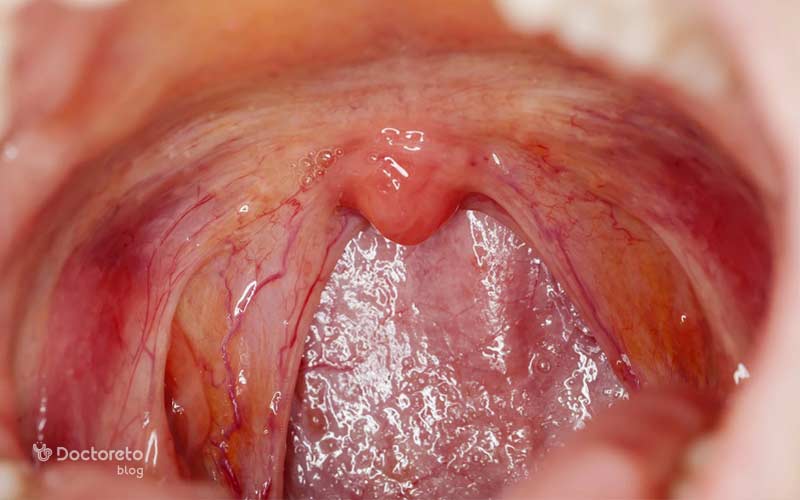

عکس لوزه طبیعی و سالم

لوزههای سالم معمولاً صورتیرنگ هستند و سطحی یکنواخت دارند. در حالت طبیعی، لوزه ها از کنارههای گلو بیرون نزده و فقط کمی قابل مشاهده هستند. زمانی که لوزهها دچار عفونت یا التهاب میشوند، معمولاً قرمز و متورم به نظر میرسند.

| لوزه طبیعی | سایر لوزهها |

|---|---|

| صورتیرنگ، سطح یکنواخت و کمی قابل مشاهده | قرمز، متورم و گاهی با لکه یا ترشح چرکی |

| در پشت گلو معمولاً بیرون نزده و اندازه طبیعی دارد. | بزرگشده یا تودهای، ممکن است فضای راه هوایی را تنگ کند و بلع یا تنفس را دشوار کند. |

| عملکرد بخشی از سیستم ایمنی و مشابه غدد لنفاوی | ممکن است چرک تجمع یابد (لوزه چرکی)، سنگ لوزه یا التهاب حاد ایجاد شود. |

| بدون درد یا علائم آزاردهنده | علائم شامل گلودرد شدید، درد هنگام بلع، درد گوش، تب، بوی بد دهان و اختلال در خواب است. |

| کریپتها و حفرههای کوچک طبیعی هستند. | کریپتهای بزرگ یا ملتهب میتوانند باعث تجمع مواد و ایجاد التهاب مزمن شوند. |